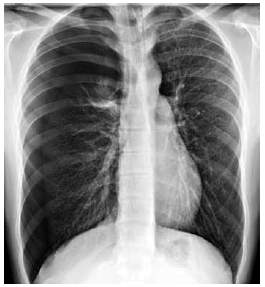

Homem de 39 anos de idade, tabagista, apresenta quadro de dor torácica intensa e dispneia de início agudo. PA: 128 x 78 mmHg, FC: 112 bpm, FR: 28 ipm e oximetria com SatO2: 95%. Não há antecedentes mórbidos e nega etilismo. ECG: taquicardia sinusal. A radiografia de tórax realizada é mostrada a seguir.

Nesse caso descrito, a melhor conduta é